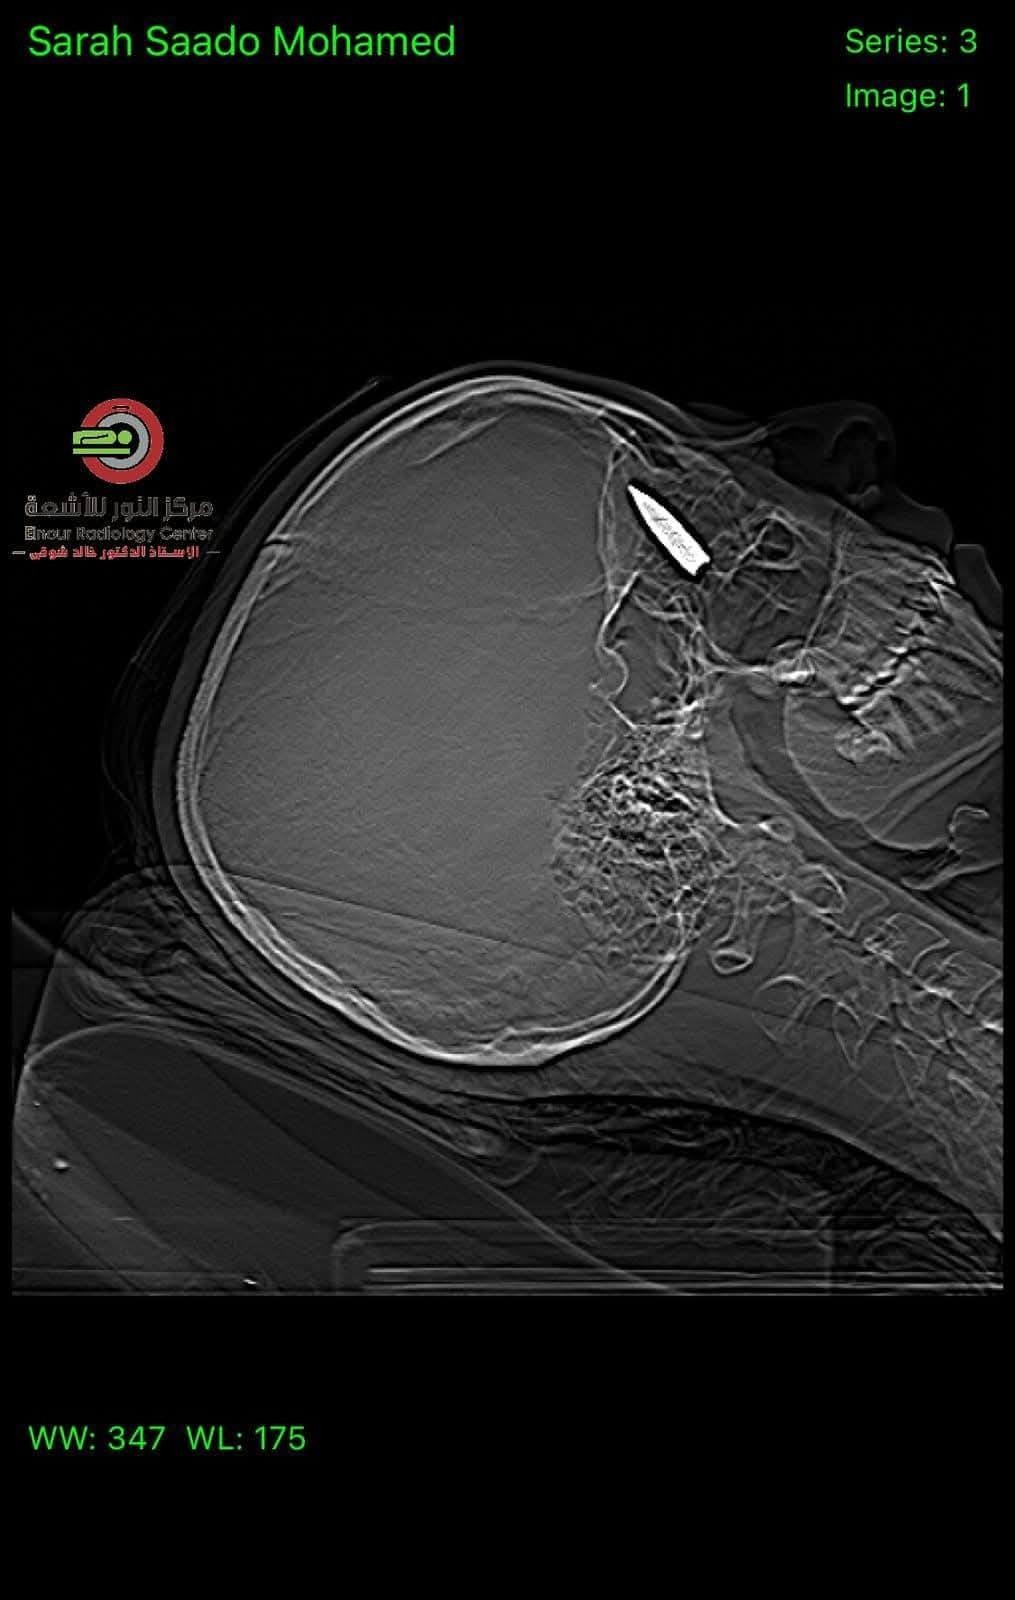

وكانت الشابة الفلسطينية قد تعرضت لإصابة بالغة نتيجة إصابتها بطلقة نارية اخترقت جمجمتها واستقرت خلف العين في منطقة حساسة، حيث تم إطلاقها من طائرة "كواد كابتر" خلال النزوح الذي تعرضت له في منطقة النصيرات.

ووصف الأطباء المصريون، العملية بأنها "بالغة التعقيد، حيث كان الطلق الناري قد استقر في منطقة حساسة داخل الجمجمة، مما كان يشكل تهديداً كبيراً على حياة المريضة".